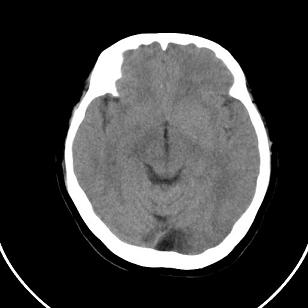

标题: CT20488:女,39岁,体检,双侧脑室有问题吗?

双侧脑室边缘呈波浪样,没有见过?

双侧脑室外缘灰质密度结节应该是尾状核的体部;枕大池前缘受压前移位,考虑囊肿

不知患者有无临床症状,双侧侧脑室边缘不规则,呈波浪状,考虑脑室周围白质软化症可能性大

影像学表现:软化灶分布于半卵圆中心和脑室周围白质,呈斑片状或长条状,多为双侧分布,脑室扩大,且脑室缘不规整。这是本症在影像学上的特点。

只有一层显示双侧侧脑室边缘不规则,呈波浪状,不排除部分容积效应,我做的话薄层再扫描一下

这个病例不符合脑室周围白质软化症

是不是应该考虑结节性硬化或者灰质移位,建议mri

支持灰质移位,mri检查有必要.枕大池蛛网膜囊肿.

1)脑灰质异位。2)双侧枕部颅骨内板下方类似扇形及弧形脑脊样低密度影;鉴别于巨大枕大池与蛛网膜囊肿之间。建议必要时行进一步检查。